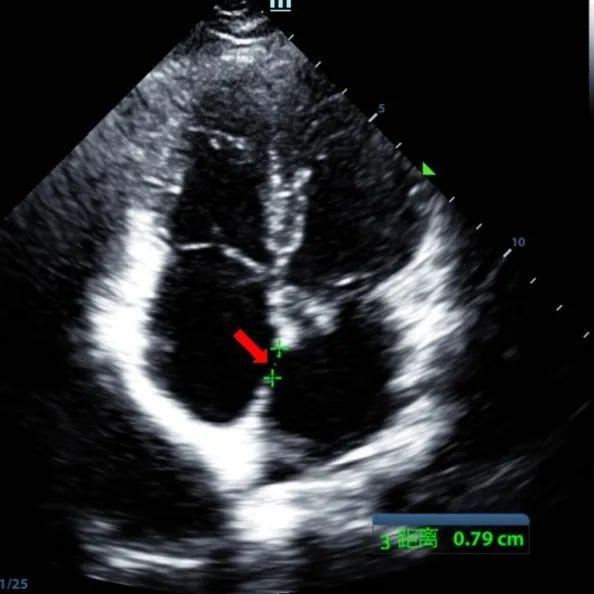

A 9-year-old male with secundum ASD (7.5–7.9 mm) was treated using a MemoSorb BDASD-I 12 mm occluder and 12F delivery system. No complications or comorbidities were noted pre-procedure.

Serial echocardiographic follow-ups showed stable device position and favorable cardiac remodeling. Gradual degradation confirmed the occluder's long-term safety and efficacy.